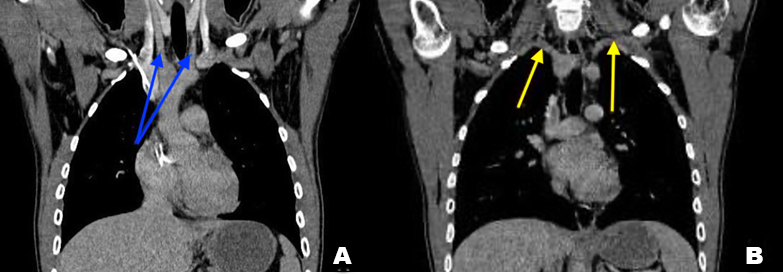

We report a case of a 27-year-old male patient, chronic smoker, presenting to our department for difficulties in swallowing evolving for several years never explored. Upper gastrointestinal (GI) endoscopy was normal. Contrast enhanced thoracic CT scan was realized showing a double aortic arch (DAA) with the ascending aorta seen splitting into the right arch and the left arch (Figure 1A). The double arch forms a vascular ring with compression of the proximal esophagus posteriorly as well as abutment and slight compression of the trachea (Figure 1B). The right and left arch have the same diameter, and each one gives rise to the ipsilateral subclavian and common carotid arteries (Figure 2). Then both arches unite posteriorly and form the descending aorta. Our scan showed no other cardiac anomaly.

Figure 2: CT C+ portal phase coronal reconstruction, in (A) showing each arch giving rise to ipsilateral carotid arteries (blue arrows), and in (B) the subclavian arteries (yellow arrows).